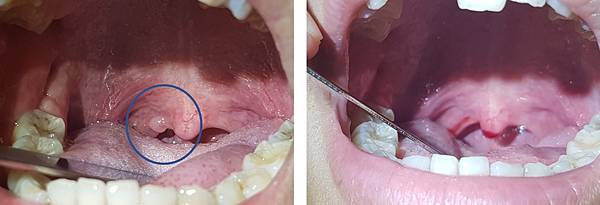

她很擔心,怎麼這麼年輕就得到腫瘤。經過詳細檢查,發現在她的懸壅垂(俗稱小舌或喉嚨滴ㄚ),有一個小小的腫塊,於是直接在門診幫她切除,並送化驗。

一個禮拜左右年輕美眉回診看化驗報告,喉嚨的傷口已經完全復原,心情也恢復輕鬆。

報告結果如同我想的一樣,乳突瘤!!